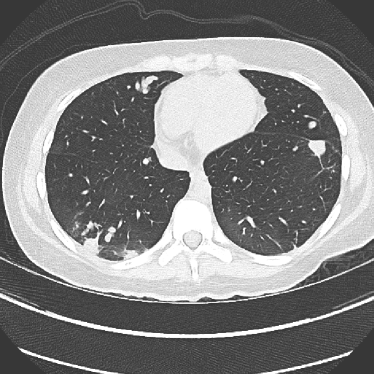

Figure 14: Qualitative clinical results from a thoracic CT staging dataset for a 12-year-old with osteosarcoma with pulmonary metastases. The clinical standard hybrid IR is shown on the left and JENG is on the right. (a) The clinical standard hybrid IR in lung window with a window center of -600 HU and a window width of 1500 HU. (b) JENG at a resolution comparable to the clinical standard, but with less noise and fewer artifacts. (c) The clinical standard hybrid IR in soft tissue window with a window center of 55 HU and a window width of 440 HU. A metastatic lung cancer nodule can be found in the left upper lobe. (d) JENG in soft tissue window at a comparable resolution, but with less noise and fewer artifacts. Note that JENG is not fully corrected for beam hardening artifacts.

Figure 15: An example cross-plane image from the same thoracic dataset as in Fig. 14. (a) A coronal-view image slice of the clinical standard hybrid IR in soft tissue window. (b) JENG at a comparable resolution but with reduced image noise and artifacts.

V.B. Clinical Cases

None of the spatial resolution and artifact reduction advantages would hold unless JENG shows image quality improvement over the clinical standard method on patient datasets. To do so, we evaluated JENG on 5 thoracic and 3 abdominal CT scans and all scans used the same parameter settings as those for the ACR phantom scan, except that the tube current and the pitch is modulated individually for each patient. The exact experiment setup was discussed in Sec. IV.. For a fair image quality comparison, we matched the resolution of JENG and the clinical standard hybrid IR and studied their image noise and artifacts.